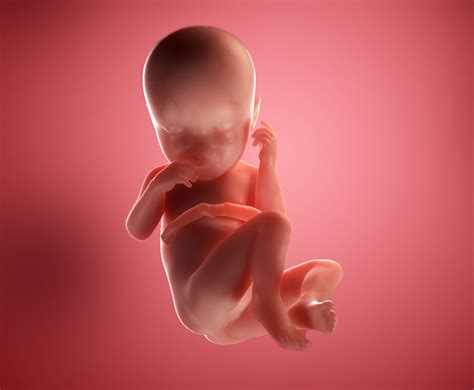

Welcoming a new life into the world is an extraordinary experience, and understanding the developmental milestones of a 37-week newborn can help parents navigate this exciting journey with confidence. At 37 weeks, babies are considered early term, and while they are generally healthy, they may still require some special care compared to full-term infants. This post will delve into the key aspects of a 37-week newborn, including their physical characteristics, developmental milestones, and essential care tips.

Physical Characteristics of a 37-Week Newborn

A 37-week newborn is typically smaller and less developed than a full-term baby. Here are some key physical characteristics:

• Size and Weight: At 37 weeks, babies usually weigh between 5 pounds 8 ounces (2.5 kg) and 6 pounds 2 ounces (2.8 kg). Their length can range from 18 to 20 inches (45.7 to 50.8 cm).

• Appearance: The skin may be wrinkled and translucent, and the baby might have a fine hair called lanugo covering their body. The head may appear disproportionately large compared to the body.

• Reflexes: Newborns at this stage have strong reflexes, including the Moro reflex (startle reflex), rooting reflex, and sucking reflex.